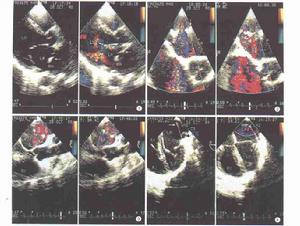

超聲心動圖:B型超聲心動圖顯示左房內,二尖瓣上方可見到異常隔膜回聲。脈衝都卜勒超聲檢查可顯示異常隔膜,並可見血流通過隔膜上的孔道以及房間隔缺損的大小,對診斷幫助很大。

超聲心動圖是診斷三房心很有價值的方法。顯示左房內異常帶狀回聲並將左房分成兩腔,二尖瓣後葉舒張期高頻撲動,而二尖瓣葉正常。然而左房內隔膜不易發現,必須仔細檢查,尤其是臨床懷疑風心病而二尖瓣正常者。